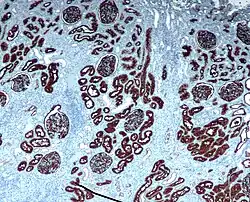

Неприлизин экспрессируется широким спектром тканей, но особенно высокий уровень белка обнаружен в почках. Это частый антиген, обнаруживаемый при остром лимфобластном лейкозе, и является важным маркёром при диагностике заболеваний у человека. Представлен на лейкемических клетках пре-B-лимфоцитарного фенотипа, которые представлены в 85 % всех случаев острого лимфобластного лейкоза[1].

CD10 применяется при гематологической диагностике, поскольку белок экспрессирован на ранних B-, про-B- и пре-B-лимфоцитах и в герминативном центре лимфатических узлов[3]. Гематологические заболевания с положительным тестом на CD10/ALL включают ангиоиммунобластную T-клеточную лимфому, лимфому Беркитта, хронический миелоидный лейкоз в бластном кризе (90 %), диффузную B-крупноклеточную лимфому, клетки фолликул лимфоузла (70 %). Острый миелоидный лейкоз, хронический лимфолейкоз, мантийноклеточная лимфома и B-клеточная лимфома маргинальной зоны характеризуются отрицательным тестом на CD10. CD10 отсутствует на клетках лимфомы, происходящих из зрелых B-клеток[4].